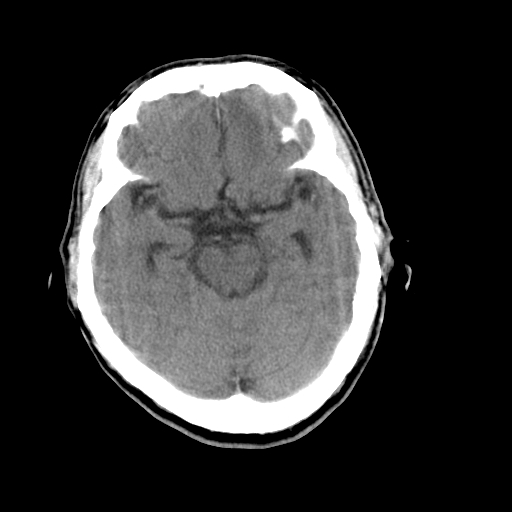

男,64岁,左侧肢体活动障碍两天。

好像有轻度积水改变。

侧脑室有点怪怪的

拟:轻度脑积水,治疗后复查。(如果你说的时间准确的话,左侧肢体活动不便,不会是脑卒中所引起,是不是高血压引起的血管痉挛呢?请结合临床)。

考虑 脑萎缩,脑积水待排

目前看是双侧侧脑室有轻度扩张,建议结合临床治疗后复查,

除侧脑室轻度扩大外无其他异常发现

考虑轻度脑积水

轻度脑积水